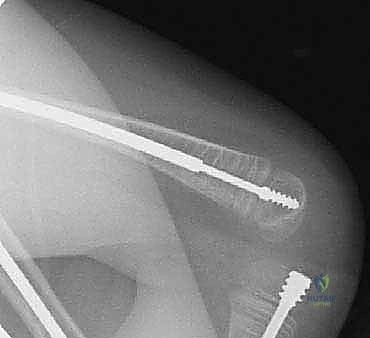

تُعد هذه العملية من أدق العمليات في جراحة عظام الأطفال، وتتطلب مهارة استثنائية كما هو الحال مع البروفيسور محمد هطيف. يتكون المسمار التلسكوبي (Fassier-Duval) من جزأين يتداخلان ببعضهما البعض (مثل التلسكوب). يتم تثبيت أحد الأطراف في أعلى العظم والطرف الآخر في أسفله. عندما ينمو العظم، ينزلق الجزء الداخلي من المسمار للخارج، مما يسمح للعظم بالنمو الطبيعي دون أن ينثني أو ينكسر.

بعد تقويم العظم وجعله مستقيماً كحبات المسبحة على خيط، يتم إدخال السلك الدليلي (Guide Wire). ثم يتم إدخال الجزء الخارجي (الأنثوي) من المسمار التلسكوبي وتثبيته في الجزء العلوي من العظم (Epiphysis).

بعد ذلك، يتم إدخال الجزء الداخلي (الذكري) من المسمار عبر الجزء السفلي من العظم وتثبيته في المشاشة السفلية. هذا التصميم العبقري يضمن حماية العظم بالكامل من الداخل.

المسمار العادي ذو طول ثابت، وعندما ينمو عظم الطفل، يصبح المسمار قصيراً ولا يحمي الأطراف الجديدة للعظم، مما يؤدي لكسرها. أما المسمار التلسكوبي فهو مصمم من قطعتين تتمددان مع نمو العظم (مثل هوائي الراديو القديم)، مما يوفر حماية دائمة للعظم طوال فترة النمو.